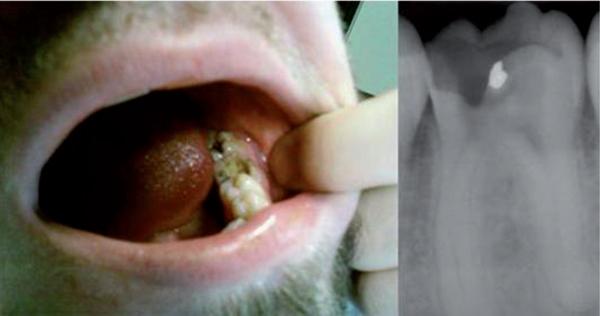

We report the clinical case and course of treatment of a 18-year-old male patient presenting with multiple hepatic abscesses associated with an untreated pyogenic dental infection.

我们报告了一例 18 岁男性患者的临床病例和治疗过程,该患者患有多种肝脓肿,与未经治疗的化脓性牙感染有关。